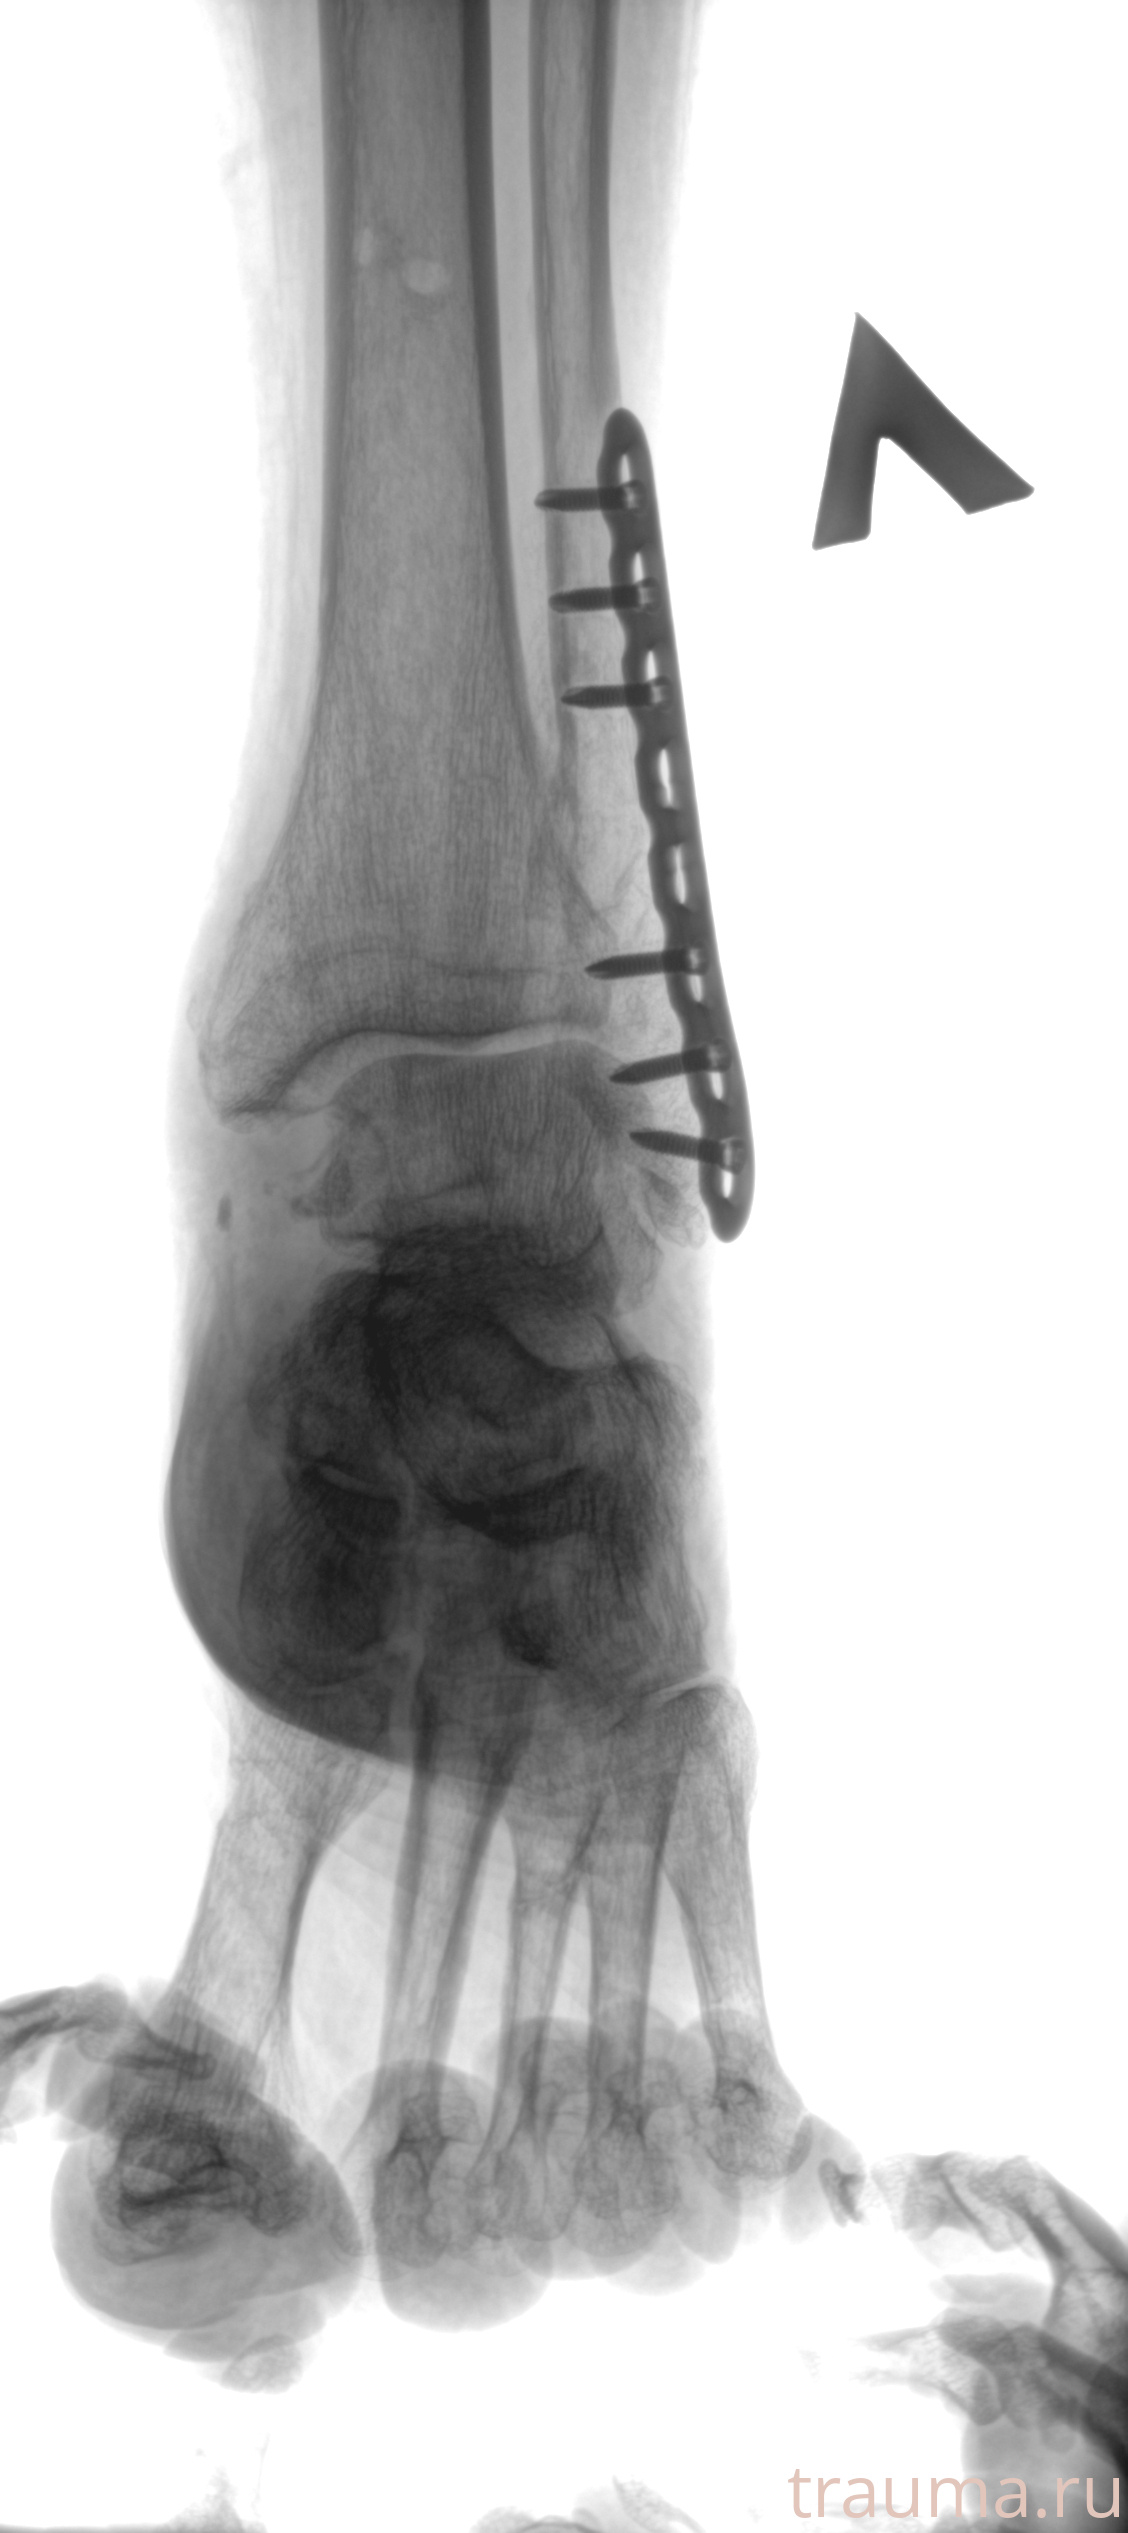

Рентгенограммы

Рентген на дому: по вашему адресу приезжает врач-рентгенолог, травматолог-ортопед с мобильным рентгеновским аппаратом, проводит диагностику травмы или заболевания, делает необходимые рентгенограммы, дает рекомендации по дальнейшему лечению. Получить качественные снимки в домашних условиях возможно благодаря уникальной методике, разработанной МосРентген Центром для института  Склифосовского